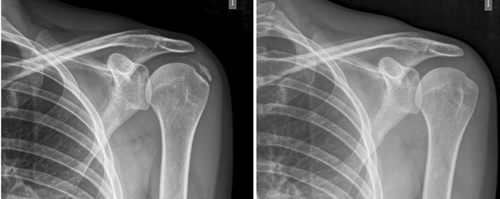

Resultados: Edad media: 54,6 años (n = 138); mujer (73,1 %; n = 101); proporción mujer/hombre 3: 1; tendón supraespinoso (94,6 %; n = 124); subescapular (5,4 %; n = 14); hombro izquierdo (55,1 %; n = 76), hombro derecho (44,9 %; n = 62); bilateral 1,4 % (n = 2); diestros 96,3 % (n = 133); antecedentes personales: tabaquismo (19,5 %; n = 27), diabetes (7,2 %; n = 10). El tiempo de enfermedad promedio fue de 6,08 meses. Dolor agudo-subagudo (menos de 3 meses) 47,1 %; (n = 65), dolor crónico (más de 3 meses) 52,9 % (n = 73). Tipo radiológico: formativo 75,3 % (n = 104), resortivo 24,7 % (n = 34). Número promedio de sesiones: 20. Complicaciones del tratamiento 2,8 % (n = 4): intolerancia/eritema/quemadura. Ocupación: administrativo 39,8 % (n = 55), trabajos manuales 60,2 % (n = 83). El dolor inicial EVA de 7,3 puntos disminuyó significativamente (p = 0,0000) después del tratamiento a 2,7. El tamaño promedio inicial de las calcificaciones fue de 10,7 mm y disminuyó significativamente (p = 0,0000) después del tratamiento a 3,8 mm. Cambio de calcificación: tasa de éxito/curación 55,7 % (n = 77), tasa de mejora 20,2 % (n = 28); tasa de fracaso del 23,9 % (n = 33). La limitación funcional disminuyó de un 10,8 % a un 2,1 %.

Results: Mean age 54.6 years (n = 138). Female (73.1 %; n = 101); female to male ratio 3:1. Supraspinatus tendon (94.6 %; n = 124), subscapularis (5.4 %; n=14); left shoulder (55.1 %; n = 76), right shoulder (44.9 %; n = 62). Bilateral 1.4 % (n = 2). Right handed 96.3 % (n = 133); Personal history: smoking (19.5 %; n = 27), diabetes (7.2 %; n = 10); disease time averaged 6.08 months; acute-subacute pain (less than 3 months) 47.1; (n = 65), chronic pain (greater than 3 months) 52.9 % (n = 73). Radiological type: formative 75.3 % (n = 104); resorptive 24.7 % (n = 34). Average number of sessions: 20.5. Treatment complications 2.8 % (n = 4): intolerance/erythema/burn. Occupation: administrative 39.8 % (n = 55), manual jobs 60.2 % (n = 83).